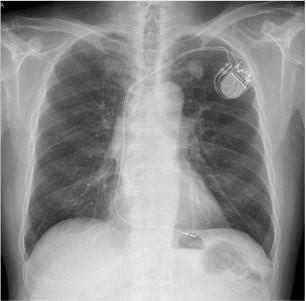

ペースメーカ植込後(X線写真)

ペースメーカ植込後(X線写真)